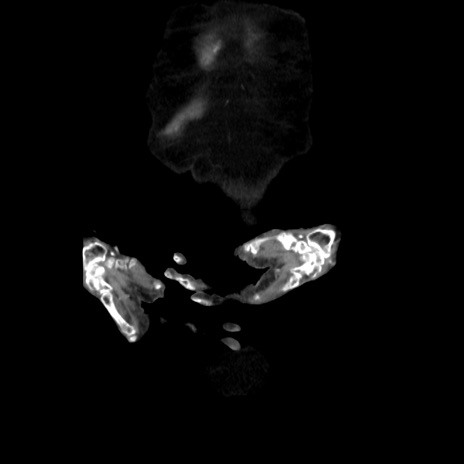

症例40(冠状断像)

矢状断像

【症例】90歳代女性

【主訴】腹痛・嘔吐

【現病歴】 食欲低下、嘔吐があり昨日他院受診。肺炎と診断され入院となる。入院後より腹部全体に圧痛あり。胃管留置され経過みていたが、症状持続するため、

当院転院となる。

【身体所見】腹部:中央に激痛あり、圧痛あり、反跳痛不明

【データ】WBC 17100、CRP 18.82